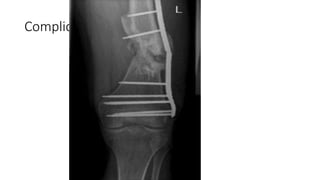

Complications

1) Malunions :

• Most commonly

associated with plating,

usually valgus

• Functional results

satisfactory if

malalignment is within 5

degrees in any plane